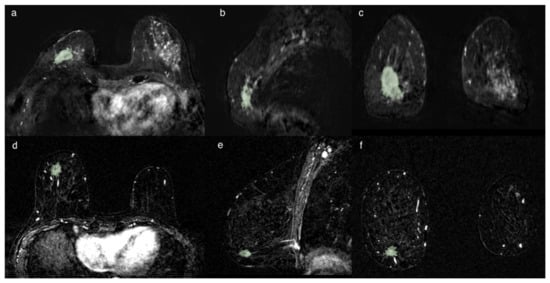

Figure 3. Two cases of breast cancer with positive and negative lymph node axillary involvement at definitive surgery, respectively. The first (ac) represented by a 32 mm mass, in 56yo patient with TN CDI tumor characterized by spiculated margins, heterogeneous enhancement with a necrotic core and a signal/intensity curve type 3 at MRI exam. The second (df) is a 13 mm nodule, in a 61 yo patient, LUMINAL A CDI, characterized by irregular margins, heterogeneous enhancement and a signal/intensity curve type 3. The segmentation has been performed in the axial image (a,d), following the margins and including the spicule characterized by contrast-enhancement. The segmentation was then optimized in the sagittal (b,e) and coronal (c,f) planes, avoiding the darker part representing the necrosis and the vessels.

The segmentation was initially always performed in the axial projections and subsequently remodeled and optimized in the other projections until the lesion was contoured optimally, avoiding the necrosis when present into the lesion, as shown in Figure 3.